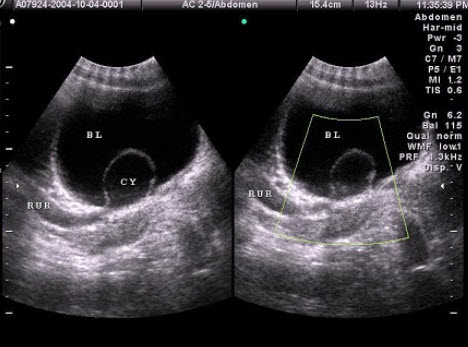

107、单项选择题

某患者因血尿就诊,下腹部声像图如图,根据图中表现及所标志的体位,最可能的超声诊断为()

A.前列腺增生并钙化

B.膀胱结石

C.膀胱癌

D.前列腺癌

E.膀胱血块